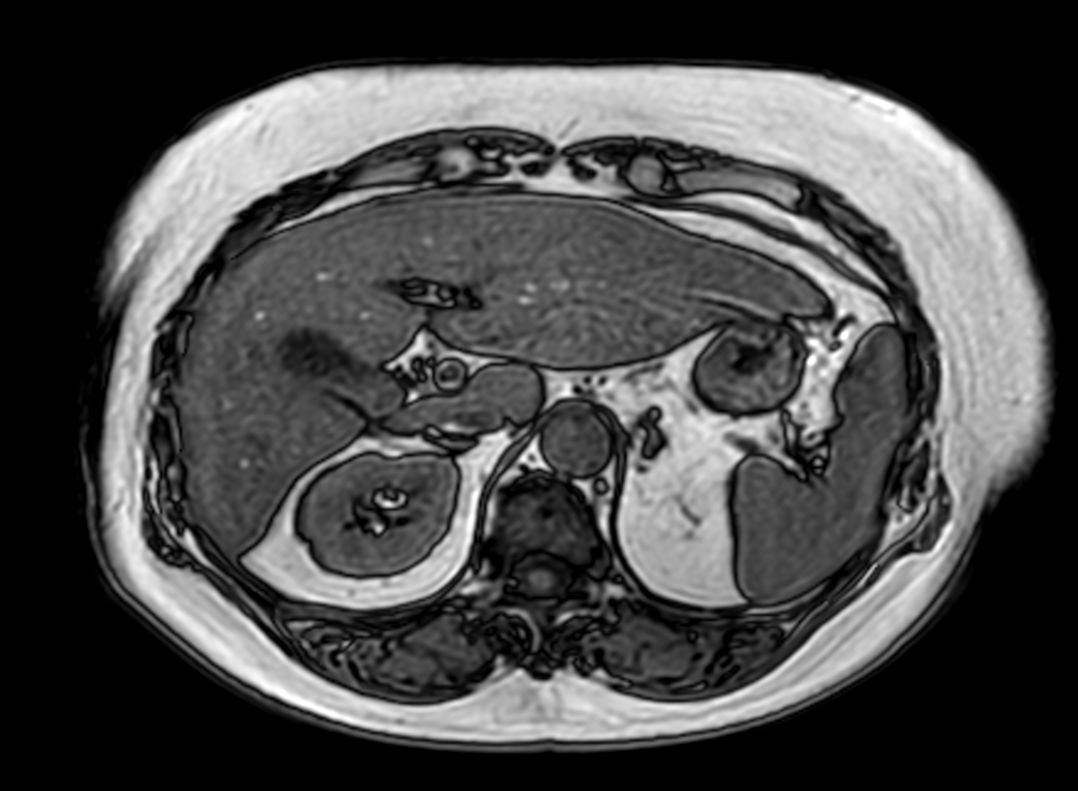

T2w TSE (single shot)

T2w TSE FatSat